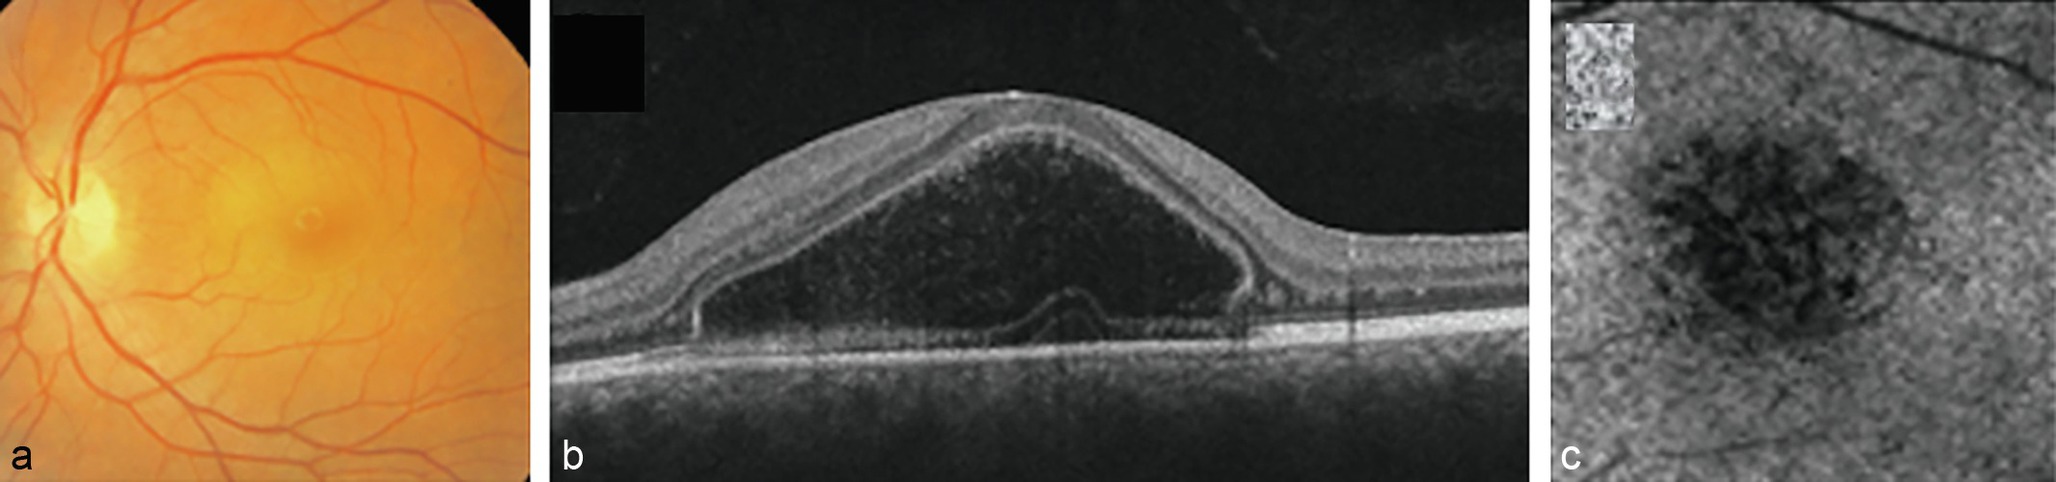

Une quinzaine de cas d'atteinte rétinienne associée à cette infection ont été rapportés. Il s'agissait dans tous les cas de patients adultes. La clinique est celle d'une maculopathie idiopathique aiguë unilatérale. La baisse de vision est habituellement sévère et brutale. Il n'y a pas d'inflammation vitréenne. Le fond d'œil montre une lésion maculaire blanchâtre, en relief, avec une hyperfluorescence en angiographie. L'OCT permet de visualiser la présence d'une accumulation de liquide intrarétinien au niveau de la couche myoïde de la rétine externe maculaire ( bacillary layer detachment ). L'OCT-angiographie montre une atteinte de la choriocapillaire. Le pronostic est bon, avec une récupération visuelle spontanée en quelques jours ou semaines. Quatre cas ont été particulièrement bien documentés dernièrement par une équipe française (fig. 50-1

Fig. 50-1

Cliché couleur montrant une lésion maculaire blanchâtre en relief (a). En OCT, aspect de kyste intrarétinien (bacillary layer detachment) (b). En OCT-angiographie, diminution du flux de la choriocapillaire au centre de la macula (c).

Source : Anjou M, Fajnkuchen F, Nabholz N, et al. Multimodal imaging of unilateral acute maculopathy associated with hand, foot, and mouth disease : a case series. Case Rep Ophthalmol 2022; 13(2) : 617-25. Reproduit avec autorisation.

) [26].